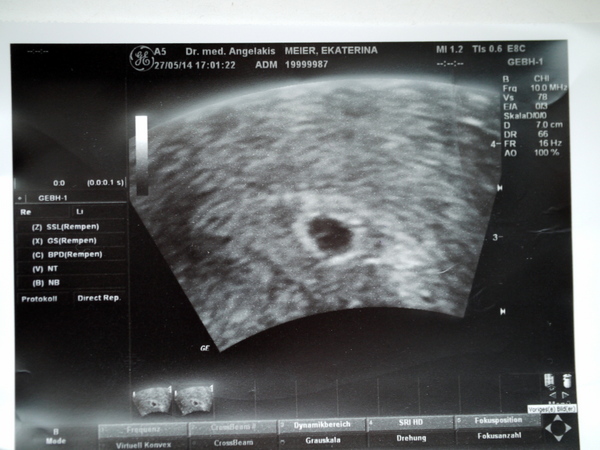

УЗИ двухплодной беременности на 5 неделе: Подборка изображений

Раздел: Калейдоскоп образов